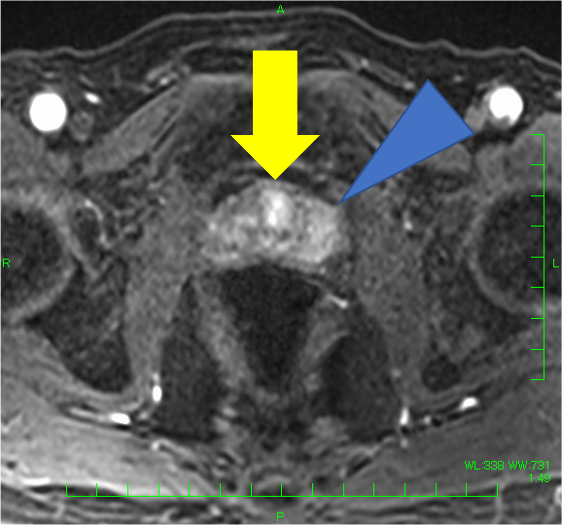

検診でPSA 4.9と上昇があり、MRIが施行された。左移行域に14mmの病変を認め、T2強調像で低信号(PI-RADS v2.1スコア4)、拡散強調像で高信号・Appar-ent Diffusion Coefficient(ADC)低下(スコア4)、ダイナミックで早期濃染を示し、PI-RADS v2.1でカテゴリー4と判定され前立腺癌が疑われた。一方、辺縁域はT2強調像で不均一低信号を呈したが、結節様の拡散強調像での強い高信号、ADC低下はなく、ダイナミックMRIでも結節様の早期濃染はなく、びまん性遷延性の染まりがみられたことから炎症性変化と判断した。生検が行われ、癌の診断であった。その後、ロボット支援下根治的前立腺摘除術が施行され、MRIと一致した前立腺癌の診断を得た(Gleason score 4+3=7, pT2N0)。

前立腺MRIでは、近年は造影なしのbpMRIでも診断精度が高いとされるが、臨床的には造影を含むmpMRIが有用な場面を経験することも多い。

本症例では、左移行域腹側の病変(14mm、T2強調像:低信号(スコア4)、拡散強調像:高信号・ADC:低下(スコア4)、ダイナミック:早期濃染: PI-RADS v2.1カテゴリー4)は、前立腺癌の判定が容易であった。一方、辺縁域はT2強調像でびまん性に不均一な低信号を呈し、癌の評価が難しい方であった。左辺縁域に小結節様のT2強調像にて低信号がみられ、拡散強調像やADCの所見は明瞭でなく癌の可能性は低いと考えたが、T2強調像での信号が明瞭で、癌を否定してよいのか悩ましい。本症例では、ダイナミックMRIも施行しており、左移行域腹側病変は早期濃染―washout パターンを呈したが、左辺縁域の小結節に早期濃染はなく、両側辺縁域とも遷延性の染まりを認めたため、辺縁域に癌はなく、両側辺縁域に炎症性変化があると断定できた。病理的にも、MRIで指摘した病変部のみ癌が同定され、その他の領域に癌はなかった。

ダイナミック造影は、拡散強調像が腸管ガスや蠕動により評価が困難な場合、小病変の有無がT2強調像、拡散強調像だけでは確信度が低い場合に有用である(特に中心域や尖部)。特に尖部病変の有無は、断端陽性率に関わるため、評価の責任を担う者としては精度の高い情報が多い方が助かる。また、精嚢浸潤や術後再発では造影が有用ということは多く知られている。カンファレンスなどで症例の供覧時に、泌尿器科医ともこの点を共有していく必要があると考えている。